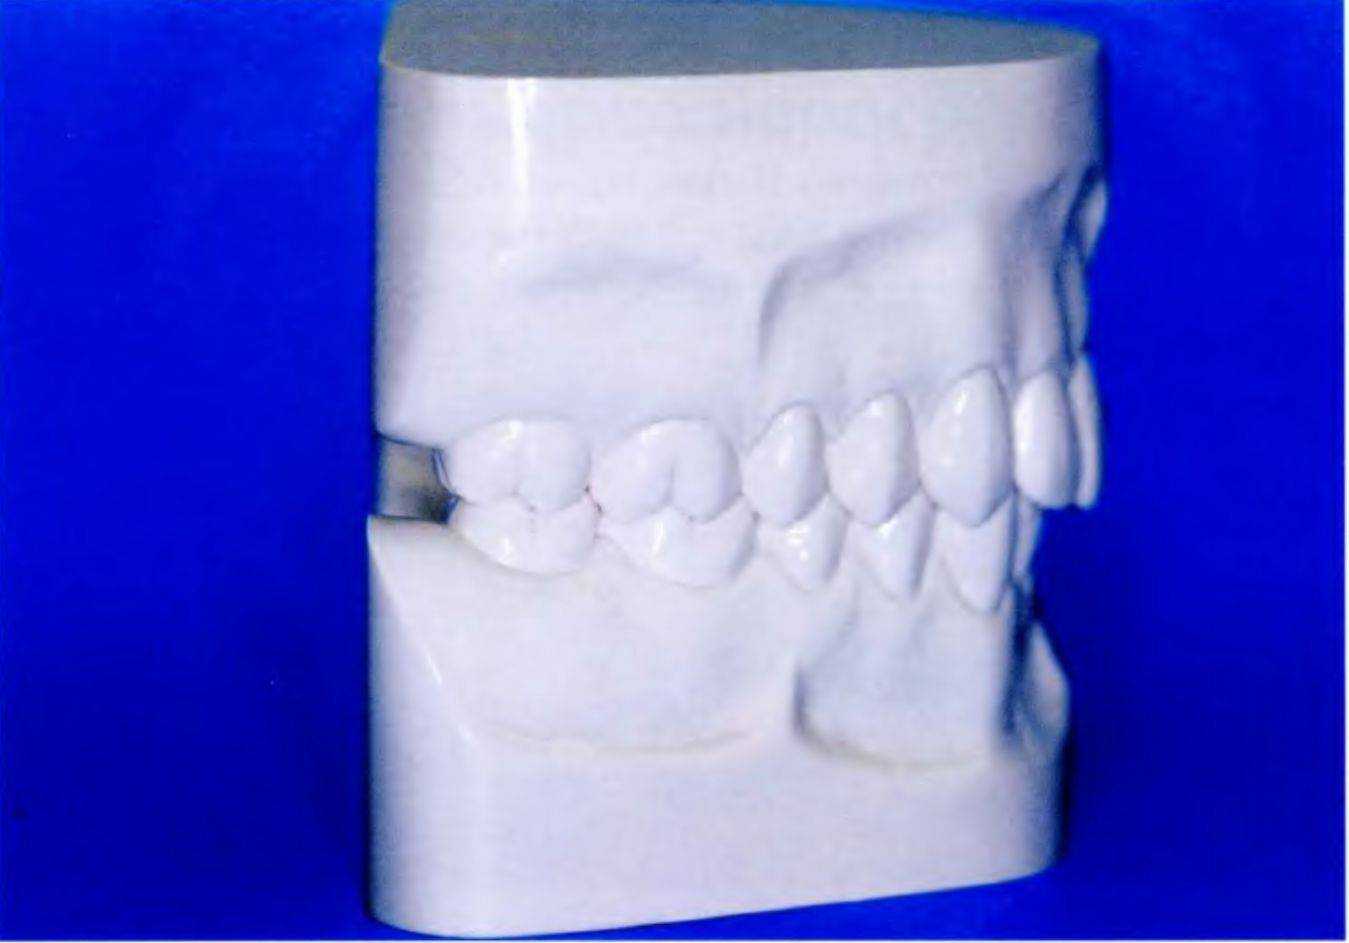

Рис. 6-9е. Модели челюстей пациента

дой из эстетических линий было на 1 мм больше, чем необходимо. Изучение моделей (рис. 6-9е) показало, что верхние резцы слишком сильно наклонены вовнутрь, что и привело к ретрузии верхней губы.